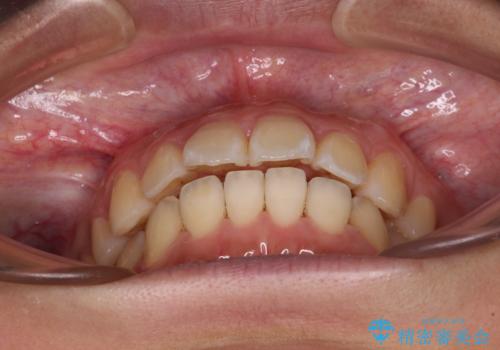

前に出ている前歯を引っ込めたい インビザライン矯正

- 前方に傾斜した上下の前歯を気にして来院された患者様です。

唇の閉じにくさや横顔のシルエットが気になるような突出感ではなかったため、インビザラインを用いて、歯列の遠心移動とIPR(歯と歯の間を削る)により前歯の傾斜を改善していくこととしました。

スムーズに終了すると思われましたが、インビザライン矯正独特の奥歯が咬み合わない状態が続き、更には遠方へ転居されたこともあり、治療期間は長引いてしまいました。